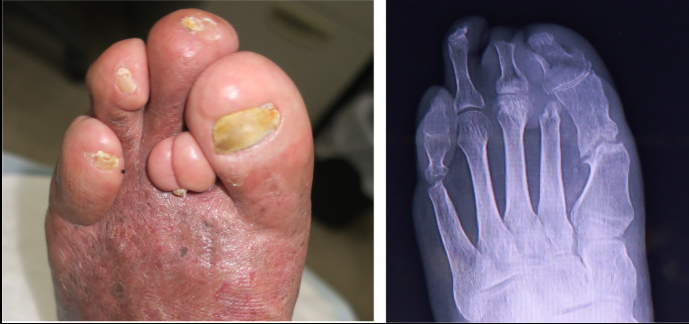

在随访中,两年内患者仍在使用定制的足部矫形器。他可以独立行走,并且足部溃疡没有复发(图4-左)。修正后的第一和第五趾有点变形。第二趾缩短,没有趾骨,第一个趾进入该空间(图4-右图)。第五趾有轻度内翻畸形。前掌形状是圆形的,似乎是因为他的鞋子。由于跖骨头切除后没有关节,软组织畸形导致了现在的足部形态。事实上,第一和第五趾的运动是灵活的。

图4